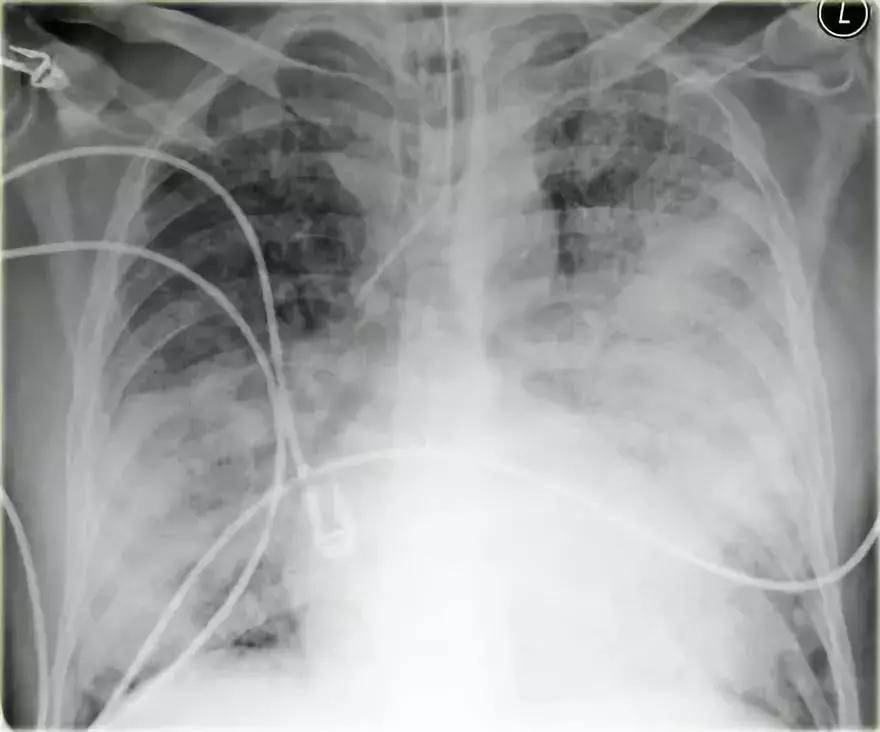

2.病例二

➢ 胸部X线显示,肺右上叶出现密度增加的模糊阴影,肺体积没有缩小

➢ 右肺门在正常的位置

➢ 箭头所示为空气-支气管征

➢ 结合适当的临床诊断,很像大叶或肺段性肺炎

➢ 然而,如果患者出现体重减轻,或症状时间持续较长,可能存在慢性实变的病因。

➢ 诊断结果为,肺炎链球菌引起的急性大叶性肺炎

图4 肺炎链球菌引起的急性大叶性肺炎